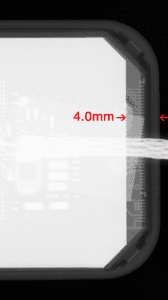

For historical reasons, most sensors place necessary electronics near the edge where the cord exits the sensor. The result is a dead space of up to 6mm, since the electronics cannot also be part of a sensor’s active imaging area. So, for bitewing purposes, the very edge used to capture the canine/premolar contact may not capture any image at all for its first 3-6mm. Clinicians who regularly place sensors instantly see this as a problem.

Figures 2a through 2d demonstrate how XDR’s imaging area extends further toward the sensor’s mesial edge. XDR has patented this approach under US #9357972B .